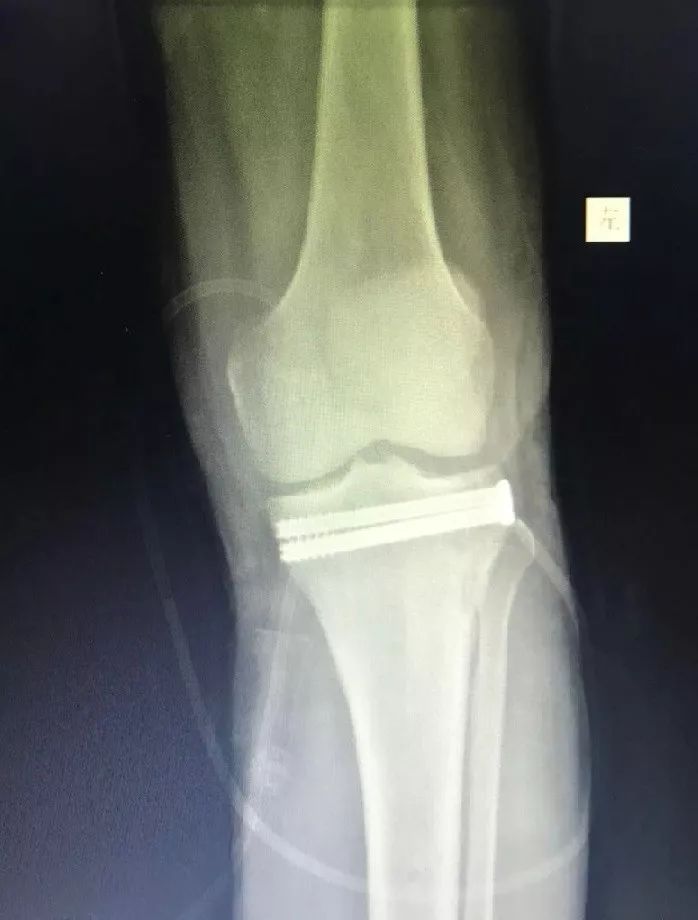

术前摄片(左)VS术后摄片(右)

“这在以前是不可想象的!像王先生这样严重塌陷的胫骨平台骨折,常规的手术方法需要大约15厘米的手术刀口,再放入长钢板固定。手术创伤大,随之而来的是剧烈的术后疼痛,漫长的恢复时间,昂贵的手术费用。对于患者,就意味着更大的经济损失和精神痛苦。”沈主任介绍说。

外科手术微创化,是医学发展的大趋势,更是广大患者的迫切要求。但是要想做到手术微创化,除了医生要有更高的手术水平,还必须要有更先进的设备来支持。“医院最近引进的天玑骨科手术机器人,简直就是微创手术小能手。有了他的帮助,以前需要反复调整的手术操作步骤,现在都是一步完成,大大缩短了手术时间,减少了手术对患者的创伤,真正做到微创化。”沈烈军主任告诉小编。

作为浙江省内第一例开展的关节镜下复位,骨科手术机器人辅助胫骨平台粉碎性骨折内固定术,它的成功开展标志着广华在骨科微创领域走在了全省的前列。不仅如此,包括脊柱科的等离子射频及椎间孔镜技术治疗椎间盘突出,关节科及足踝外科运用关节镜技术治疗肩、肘、腕、髋、膝及踝的关节内疾病等微创治疗手段也在广华蓬勃发展。